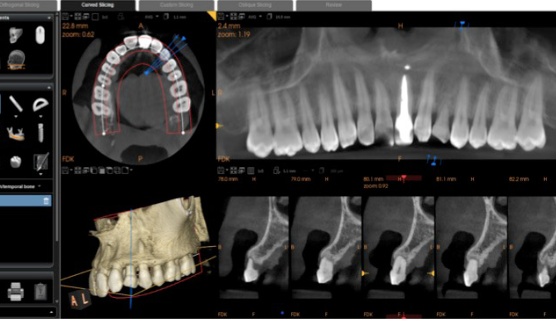

CBCT analysis within CS 3D Imaging software showing cross-sectional views of the implant site

Step 2 CBCT volume analysed in CS 3D Imaging software. Cross-sectional views confirm bone dimensions and root resorption on the UL3.

Step 3 — Prosthetic-driven implant planning. This is the key step. The CS 3D Imaging Prosthetic-Driven Implant Planning module automatically merged the CBCT volume with the intraoral scan — aligning hard tissue (bone) with soft tissue (gingiva and teeth) in a single view. The implant was then positioned using a crown-down approach: the ideal restoration position determined the implant axis, not the other way around.

CS 3D Imaging automatically merging CBCT and intraoral scan data for prosthetic-driven planning Implant position planned using crown-down approach in CS 3D Imaging

Step 3 The Prosthetic-Driven Implant Planning module in CS 3D Imaging software automatically merges the CBCT and intraoral scan. The implant is positioned based on the ideal crown position — not just the available bone.